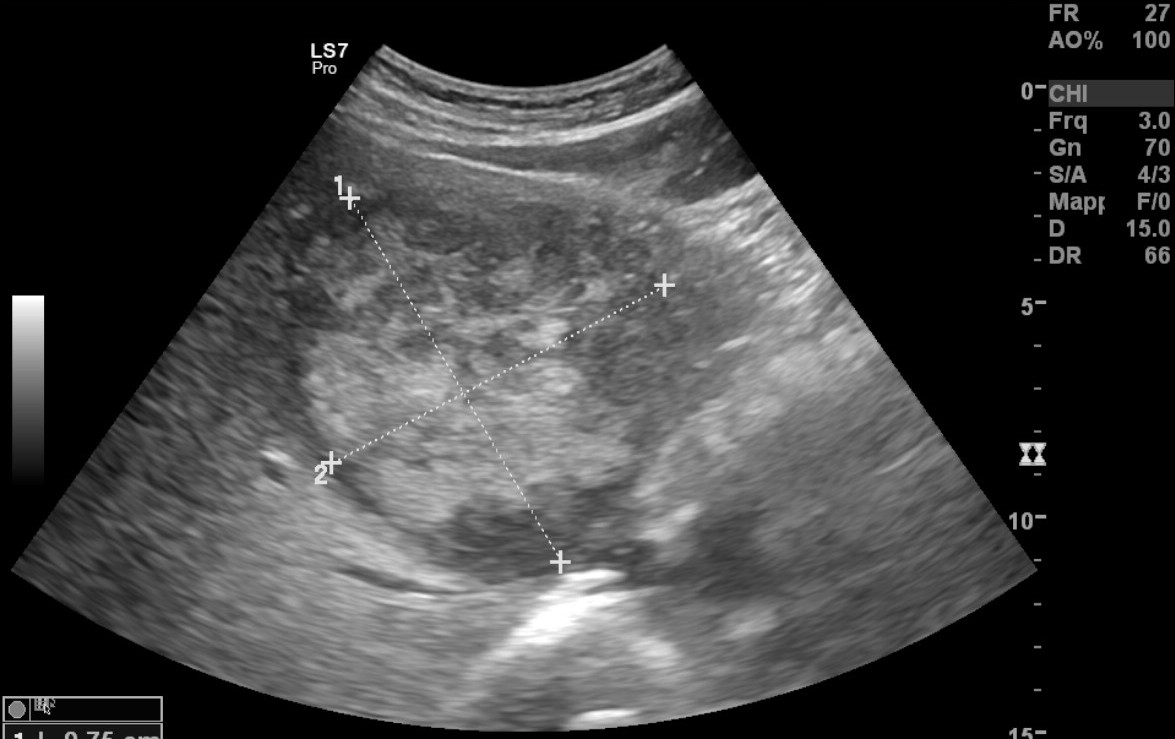

Ad oggi sono state identificate con l’ecografia addominale prevista dal protocollo, 9 neoplasie del parenchima epatico: 5 angiosarcomi (Fig. 1-4) (di cui 2 viventi) e 4 epatocarcinomi (Fig. 5-7) (di cui 1 vivente), successivamente sottoposte a studio TC e tutte confermate dalla diagnosi istologica.

Fig.3. Caso 2 di angiosarcoma epatico

Fig.4. Caso 2 di angiosarcoma epatico